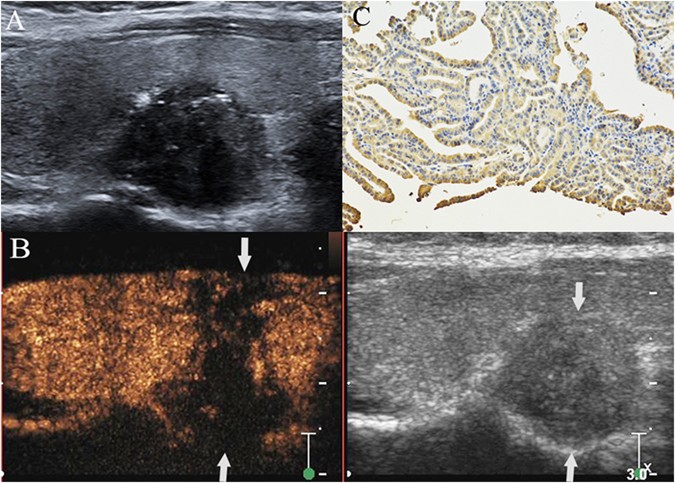

Figure 1

PTC with cervical LNM. A hypoechoic nodule with ill-defined margin, irregular shape and some microcalcifications was found at the lower pole of the right thyroid lobe in a 34- year– old female patient (A). The thyroid focal posterior capsular was bulged by nodule. The size of nodule was 1.6 cm × 1.5 cm × 1.0 cm. CEUS showed that a heterogeneous low-enhancement in nodule (left image) and its area (1.8 cm × 1.6 cm × 1.2 cm) was larger than the nodule region displayed on grey-scale image (right image) (arrow). Both the anterior and posterior thyroid capsular were broken and invaded by the nodule (arrows) (B). Intense expression (+++) (arrow) of matrix metalloproteinase-9 was found in the cytoplasm of the malignant cells of a PTC sample, as shown by the brown staining (magnification, ×200) (C). Surgical results: PTC with ipsilateral region III-V and central compartment region LNM.